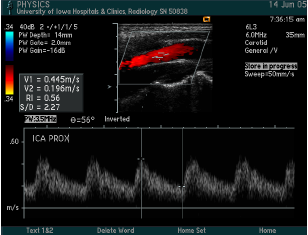

what measurements are taken?

what is calculated?

Common carotid artery

Internal carotid artery proximal

Internal carotid artery distal

External carotid artery

Vertebral

Subclavian

Peak systolic velocity, Peak end diastolic velocity

ICA/CCA ratio

what vessel is this waveform likely from?

ICA (proximal), below is distal